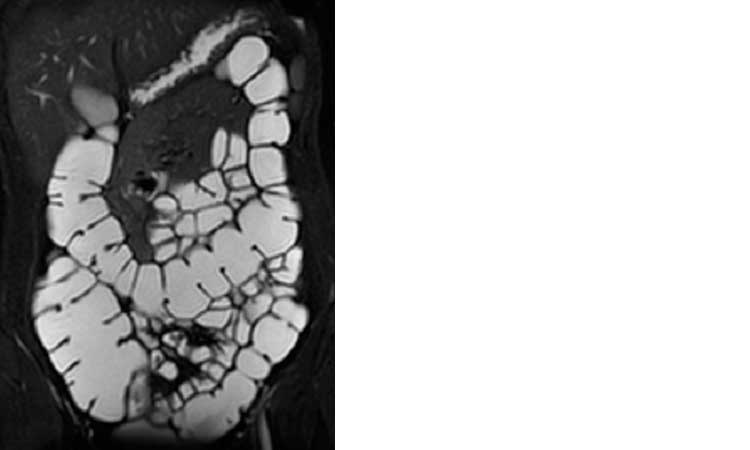

EnteroRM: l’esame consente lo studio dell’intestino e risulta particolarmente utile nelle patologie infiammatorie croniche come il morbo di Crohn.